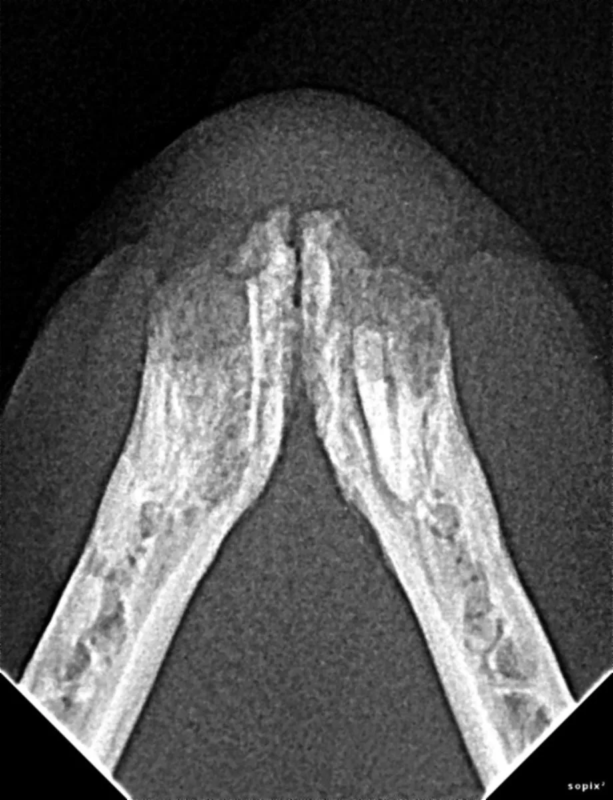

Cone Beam Computed Tomography

The Center now provides advanced imaging via cone beam CT. Cone beam CT is excellent for visualization of bony structures of the skull, nasal cavity, teeth, and ears. Cone beam CT is especially helpful for diagnosing dental disease and evaluation of jaw fractures. It can also be useful for evaluating the sinuses and tympanic bulla. Cone beam CT can be used in conjunction with nasal biopsy and culture to evaluate nasal discharge whether chronic or acute.